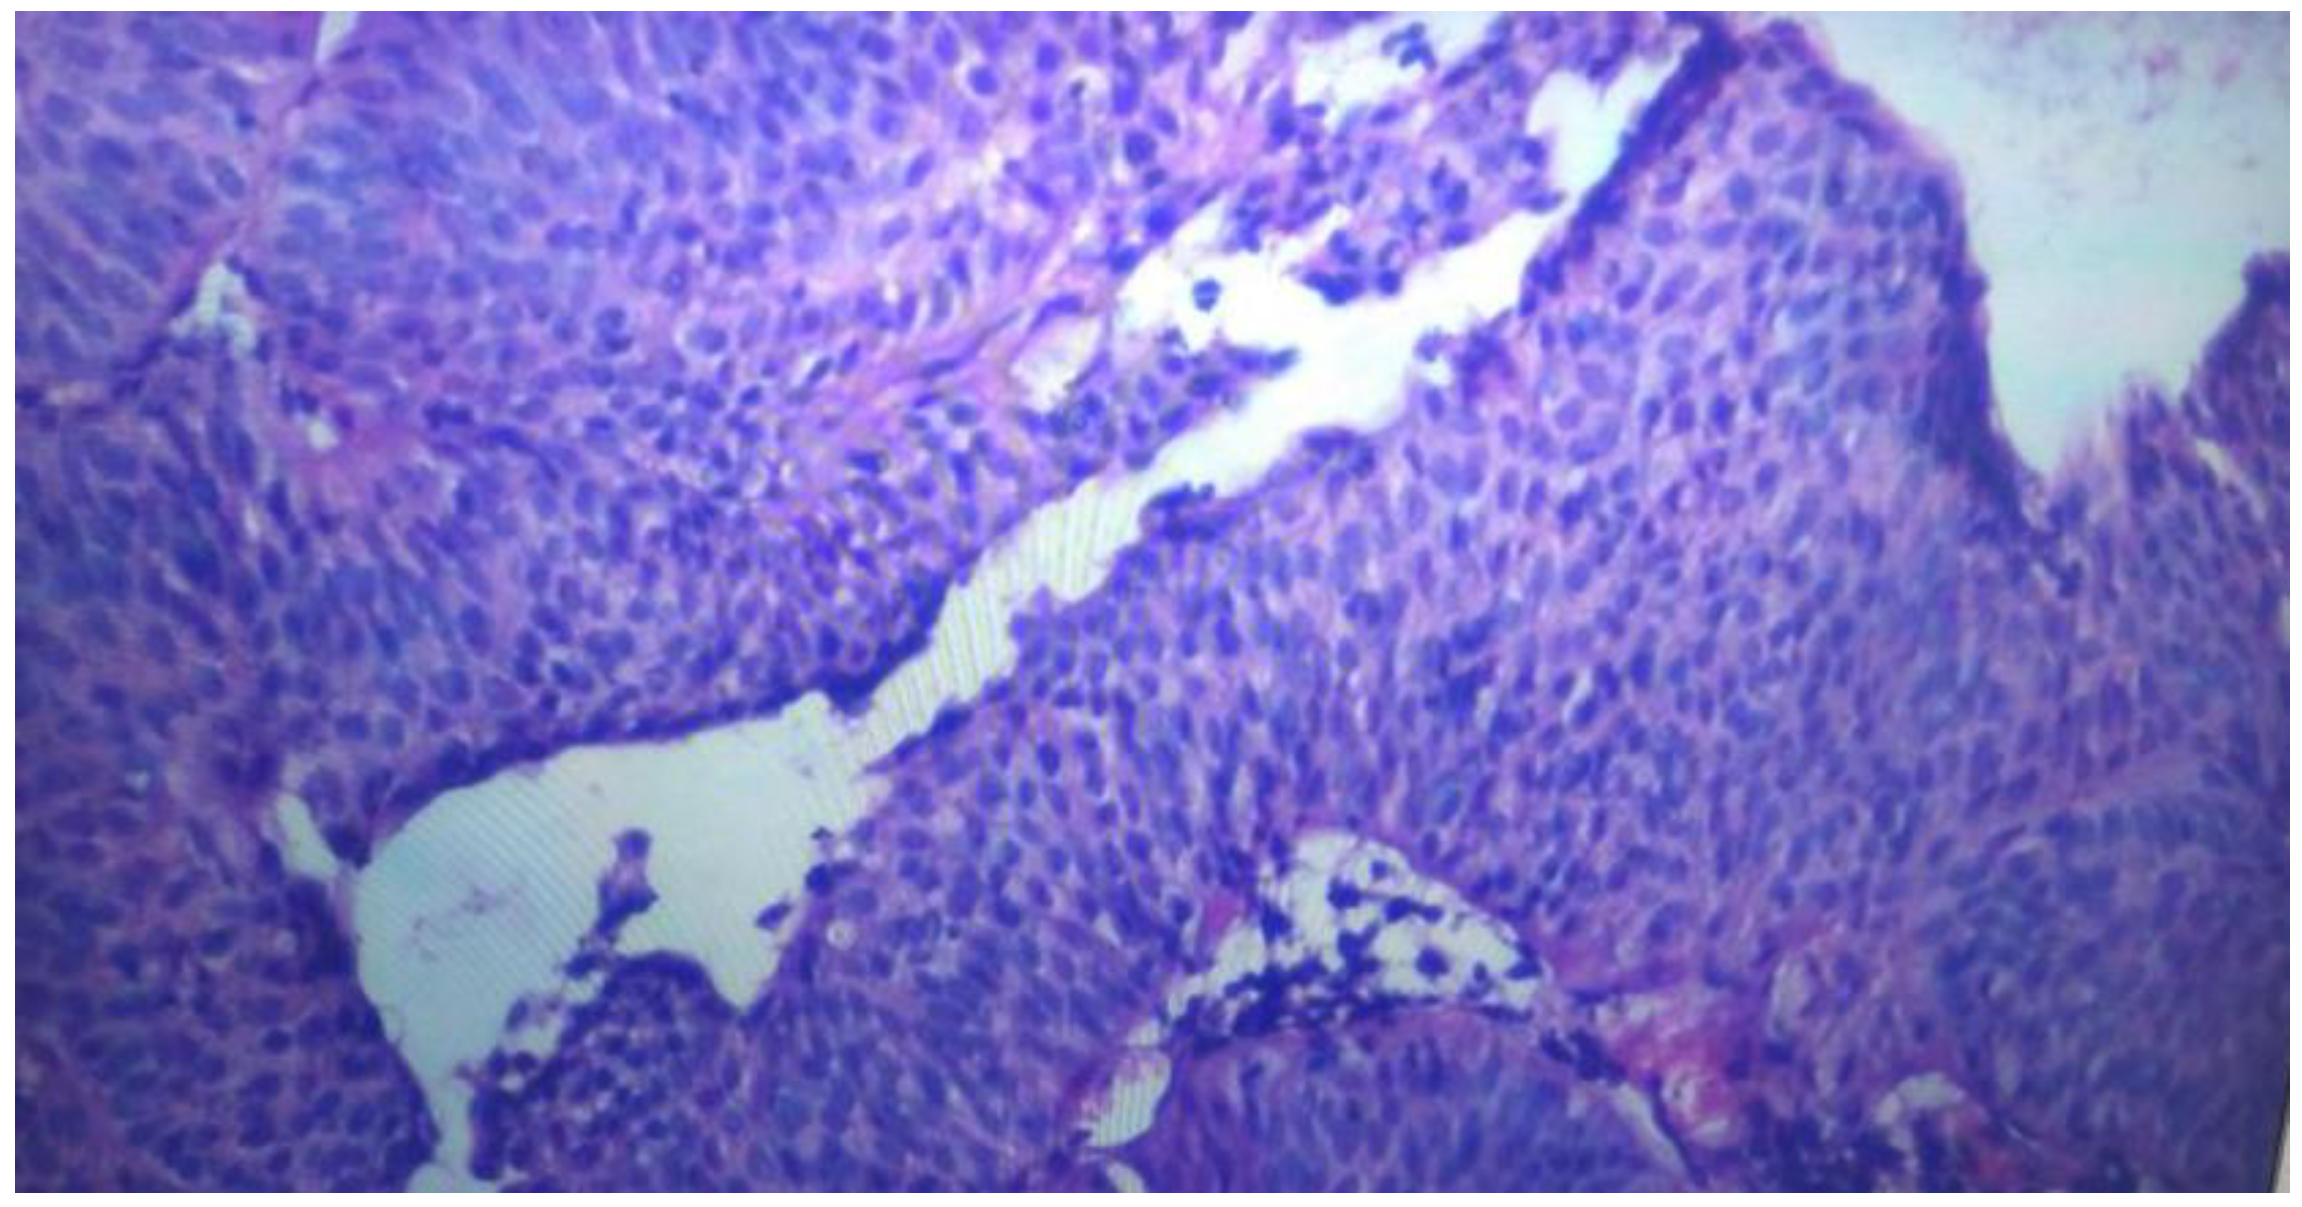

- ✓ Estudio histológico: se describen finos haces musculares que de forma discontinua se disponen paralelamente a la membrana basal y se acompañan de vasos cuyas paredes son gruesas. Finalmente la submucosa es el tejido conectivo que se sitúa entre la muscularis mucosae y la muscular propia. Llamando la atención células neoplasicas que invaden zona la zona situada entre la membrana basal y la muscularis mucosae, estando en relación con carcinoma de células transicionales de vejiga de bajo grado.(Figura 4)